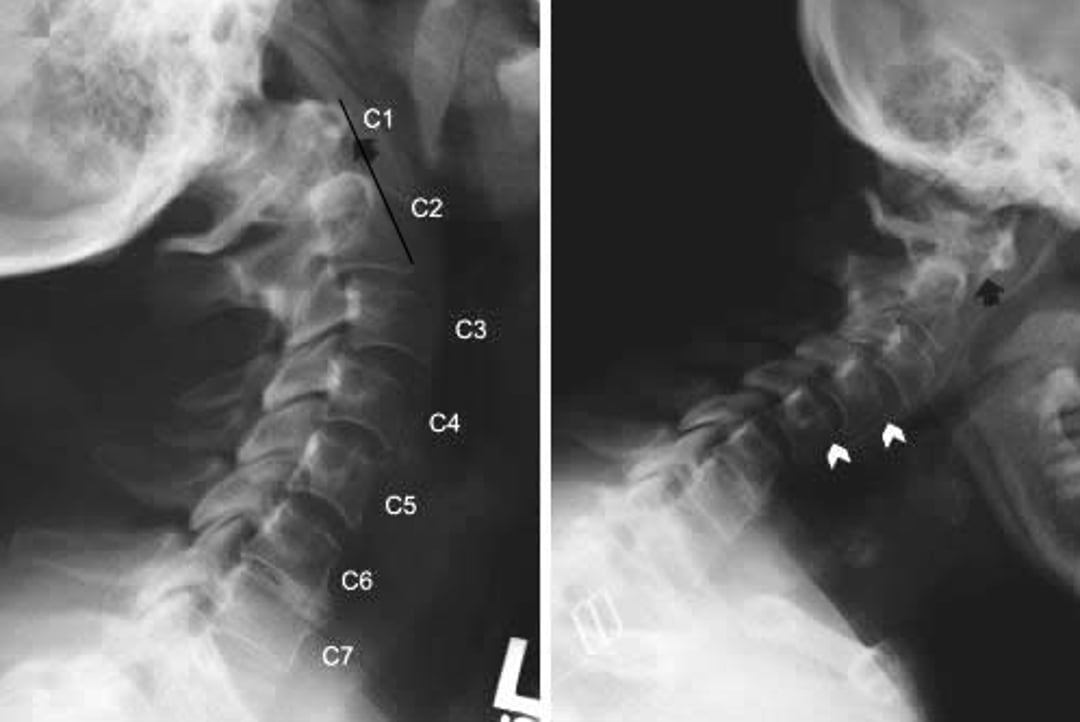

Атлантоаксиальный подвывих

Рентгенограммы шейного отдела позвоночника показывают атлантоаксиальный подвывих и субосевой подвывих у пациента с ревматоидным артритом. Рентгенограммы шейного отдела позвоночника в боковой проекции были сделаны при разгибании (слева) и сгибании (справа) шеи. При сгибании передняя дуга С1 далеко впереди зубовидного отростка С2 (позади черной стрелки), что указывает на передний подвывих. Этот признак не очевиден в разгибании (черная стрелка), указывающем на то, что атлантоаксиальный подвывих подвижен. Субаксиальная трансляция (белые стрелки) также наблюдается на уровнях C2-C3 и C3-C4 в экстензии, а также на уровнях C3-C4 и C4-C5 в флексии.